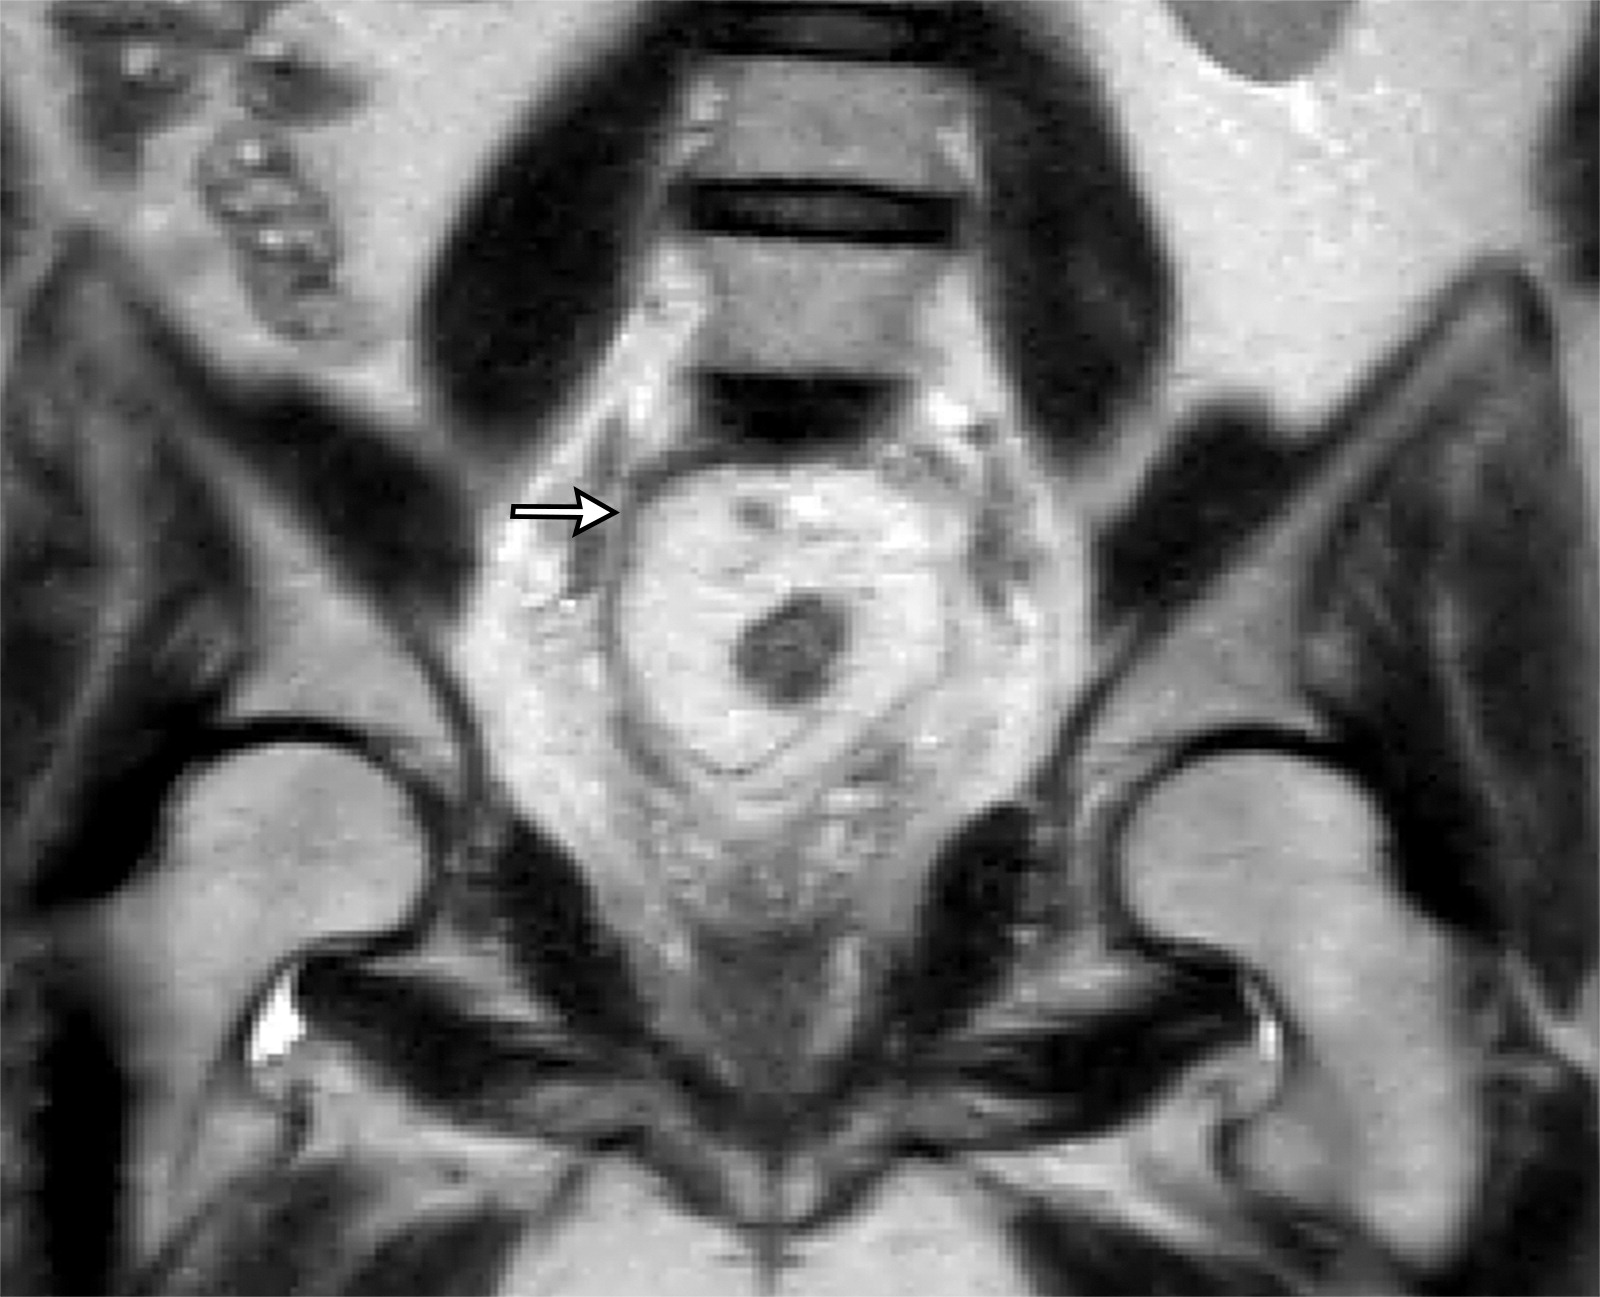

50岁以上男性骨盆和盆底的MRI解剖。

提肛肌(LA),由耻骨直肠肌(PR)、耻骨尾骨肌(PC)和髂尾骨肌(IC)组成;尾骨肌(C),前列腺(P),闭孔内肌(OI),会阴浅横肌(STP),球海绵体肌 (B), 坐骨海绵体肌(ISC),肛门外括约肌(EAS),肛门内括约肌(IAS),直肠(R),尿道括约肌(SU),也称为尿道外括约肌(U),它包围着整个膜性尿道。6774449af17bb1b8df6e83ab4e9fa158.jpeg